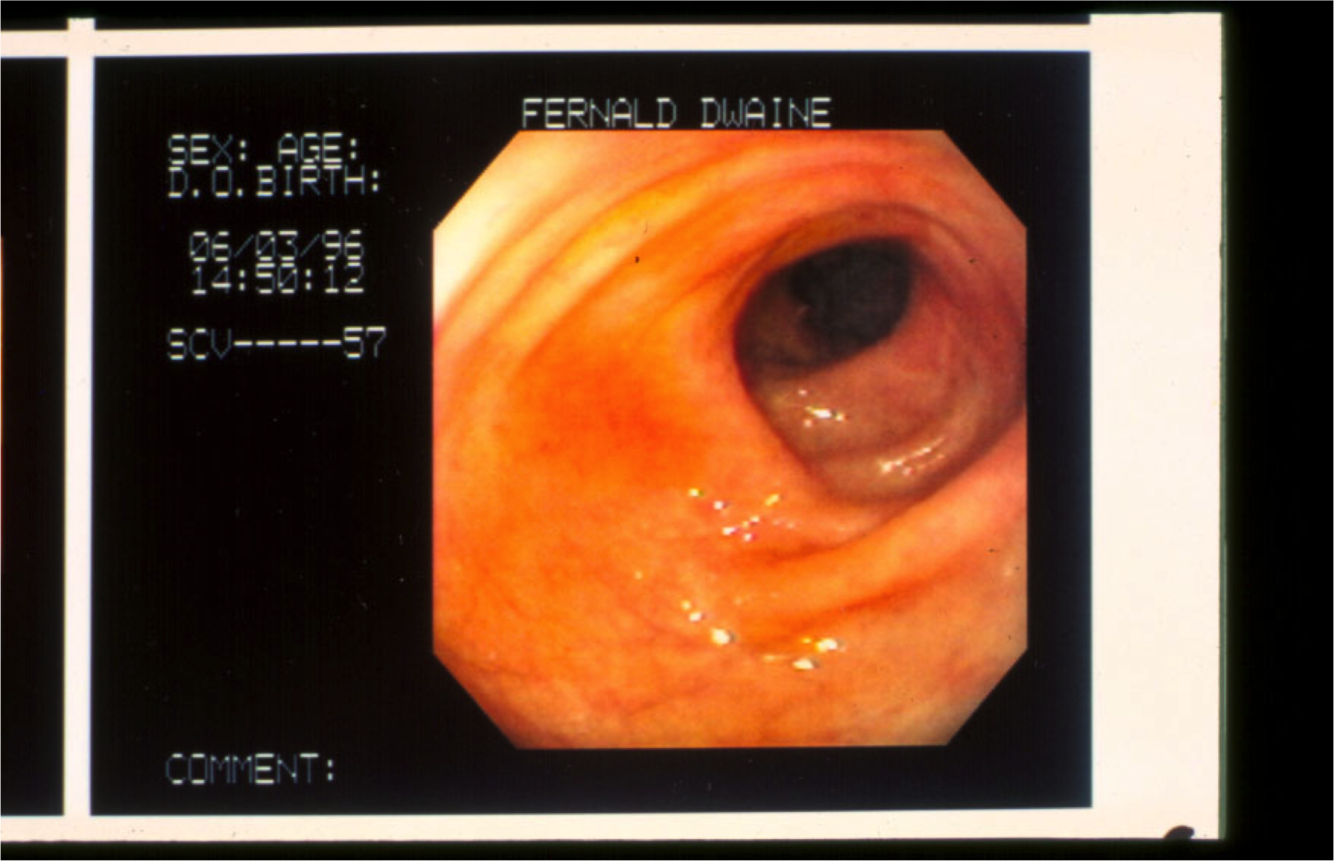

What is this picture of? What else could it be?

Normal appearance of colon.

Could be normal, could also be microscopic colitis (will see histo changes on biopsy)